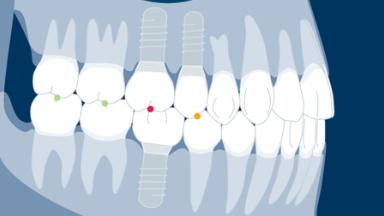

Quando os implantes são instalados e restaurados com as próteses finais, alguns princípios devem ser seguidos para obter um bom ajuste e sucesso a longo prazo da prótese. Os princípios gerais para a entrega de uma prótese implantossuportada são muito semelhantes àqueles para a entrega de uma prótese suportada por dente. No entanto, a complexidade é maior quando se utilizam próteses implantossuportadas, uma vez que elas podem ter múltiplos componentes que se encaixam muito precisamente ao longo de caminhos limitados de inserção. Além disso, essas próteses precisam ser entregues em implantes rigidamente fixados. Todos esses fatores tornam isso um procedimento muito mais rigoroso. Portanto, é importante ter um protocolo para garantir que as etapas corretas sejam seguidas, a fim de minimizar o risco de complicações e de poder verificar se o procedimento foi realizado corretamente. Também é importante poder fornecer informações de linha de base sobre a prótese contra as quais você pode comparar a condição ao longo do tempo.

- descrever como avaliar uma prótese e ensaiar sua montagem

- descrever os passos da prova e verificar se uma prótese é clinicamente aceitável